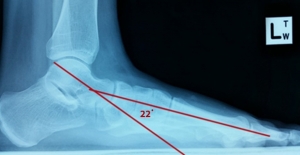

Prior to starting treatment the lateral x-ray showed the talus angle was 22° drop on the left and 11° drop on the right. After treatment the lateral x-ray showed the talus angle was 15° drop on the left and 1° drop on the right.